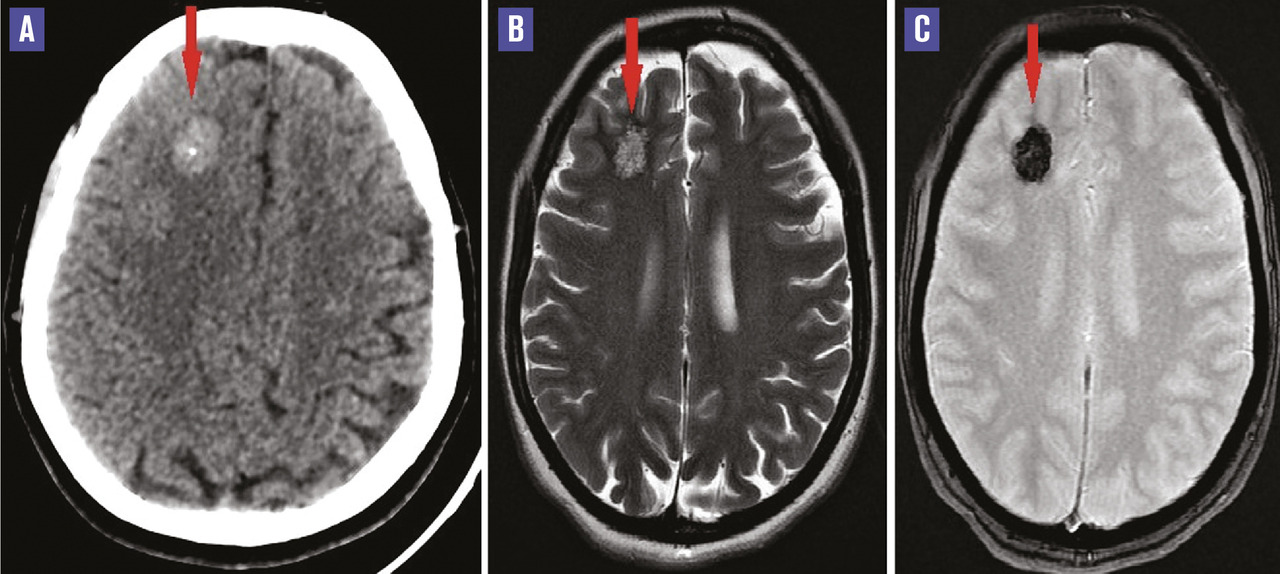

Cette femme de 43 ans, sans antécédent particulier, consultait aux urgences pour une crise convulsive tonico-clonique généralisée. À l’examen clinique post-critique, la patiente était consciente et stable. La tomodensitométrie (TDM) cérébrale montrait une lésion frontale juxtacorticale droite, spontanément dense contenant une calcification et non rehaussée après injection de contraste (fig. A ). Sur l’imagerie par résonance magnétique (IRM), la lésion apparaissait en hypersignal hétérogène contenant quelques hyposignaux sur les séquences pondérées T2 et T1, avec un hyposignal hétérogène sur la séquence T2* réalisant l’aspect en « pop-corn » (fig. B et C ). Devant le contexte clinique et cet aspect en « pop-corn », le diagnostic de cavernome frontal droit a été retenu. La patiente a été mise sous traitement symptomatique, avec persistance de quelques rares épisodes convulsifs.

Les cavernomes sont des malformations vasculaires caractérisées histologiquement par des formations capillaires dilatées (cavernes), entourées d’une paroi endothéliale et d’un fin tissu conjonctif sans interposition de tissu nerveux. C’est une pathologie bénigne mais potentiellement grave en raison du risque d’hémorragie, qui peut être fatale. Le tableau clinique est varié et non spécifique, dominé par les crises convulsives surtout dans les localisations corticales et l’hémorragie. La TDM, non spécifique et parfois normale, peut révéler une lésion corticale ou juxtacorticale, spontanément dense, légèrement inhomogène, siège de calcifications dans 40 à 50 % des cas, entourée ou non d’un halo hypodense périphérique. L’IRM est l’examen de choix. Non pathognomonique, mais très caractéristique, l’aspect typique est celui de « pop-corn » ou « poivre et sel », associant hyper- et hyposignal sur les séquences pondérées T2, entouré par une fine couronne hypo-intense en T1 et T2.1 En fonction de leur cause, on distingue les cavernomes sporadiques (les plus fréquents) dont l’étiopathogénie demeure encore obscure, les cavernomes familiaux, secondaires à une mutation génétique à transmission autosomique dominante, et les cavernomes radio-induits.